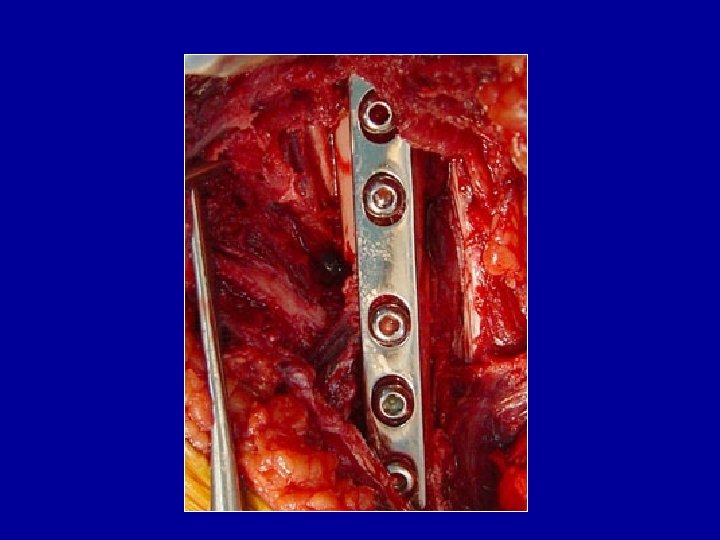

Ostéosynthèse du tibia par plaque vissée Plaque sur la corticale externe ou interne